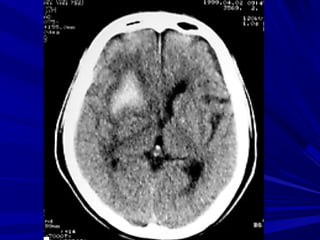

Fogging effect: Hiện tượng đồng đậm độFogging effect: Hiện tượng đồng đậm độ

vùng nhồi máu ở ngày 14-21 do tăng thựcvùng nhồi máu ở ngày 14-21 do tăng thực

bào hoặc xuất huyết vi thể, khi đó vùngbào hoặc xuất huyết vi thể, khi đó vùng

nhồi máu rất khó nhận thấy.nhồi máu rất khó nhận thấy.

Một số trường hợp có hiện tượng tăngMột số trường hợp có hiện tượng tăng

quang do xuất huyết trong vùng nhồi máuquang do xuất huyết trong vùng nhồi máu

vào sau ngày thứ ba.vào sau ngày thứ ba.

Fogging EffectFogging Effect

24 giờ 11 ngày 4 tháng